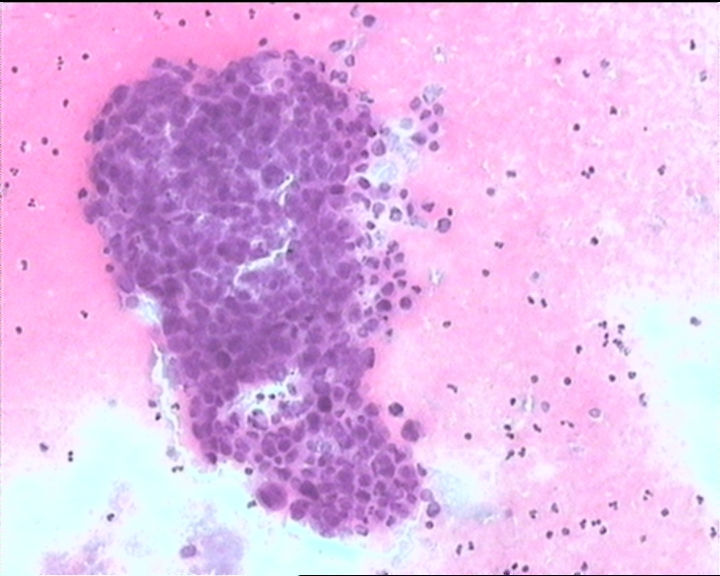

24小时尿离心图片

制片质量不好,无法判读。见部分细胞胞浆空泡,边缘清楚,来源自正常的尿路上皮细胞。有部分细胞看似染色质呈细颗粒状,分布不均匀,在这样的制片条件下不能确定是否倾向非典型表现,三维立体结构显现不清楚。另外患者的病史对于细胞病理的诊断非常重要,注意尿液的取材时间和部位。

本例细胞核大小不一,部分核形态不规则,对比周围的小淋巴细胞,细胞核明显增大。倾向恶性肿瘤,尿路上皮癌可能。如果包块在膀胱内,建议膀胱镜取活检。

脱落细胞有时HE染色核显示不满意,瑞氏染色反而效果很好,可以同时染一张瑞氏染色试一试。

尿路上皮肿瘤细胞

膀胱内有肿块,活检低非浸。

恶性肿瘤(倾向于癌)